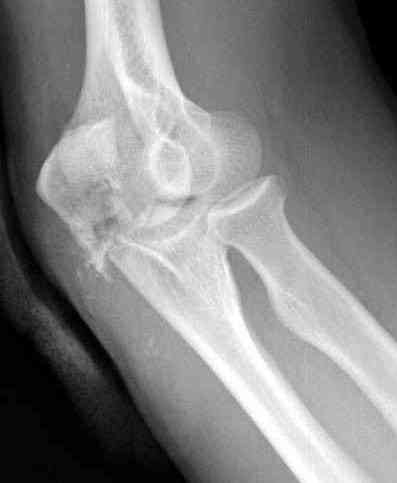

Здесь выставлены несколько случаев и варианты фиксации локтевого отростка, некоторые в комбинации с другими переломами.

1 вариант применен ACUMED локинг пластина

2 вариант

перелом локтевого отростка с переломом головки лучевой кости (использованы 2 мм шурупы)

3 вариант

перелом с capitelum humerus и проксимальной трети улна